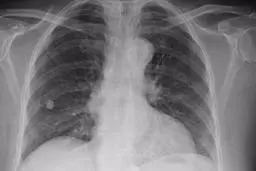

بیماری سل براحتی در هوا شناور میماند مراقب باشید

امروزه یکی از بزرگترین مسائل بهداشتی جهان، بیماری سل است.…